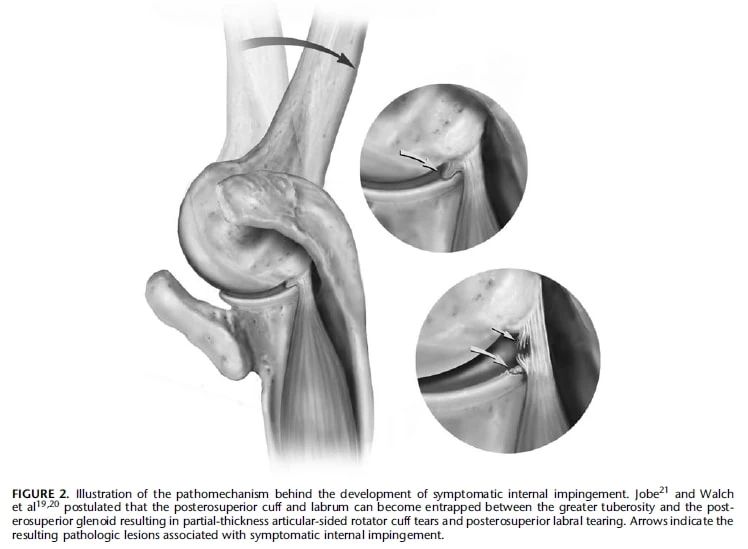

El pinzamiento interno del hombro es un término utilizado para describir un grupo de síntomas que se producen cuando los tejidos blandos del manguito de los rotadores y la cápsula articular del hombro quedan atrapados o comprimidos entre la glenoides (parte del omóplato) y el húmero (hueso de la parte superior del brazo). Esto suele ocurrir cuando el hombro está en una posición determinada, como cuando está en abducción (alejado del cuerpo) y en rotación externa (girado hacia fuera). Es diferente del pinzamiento externo, en el que el manguito y la bursa quedan pinzados en las estructuras del arco coracoacromial. La causa exacta del pinzamiento interno sigue siendo objeto de debate, pero parece ser un fenómeno normal en determinadas posiciones del hombro. Los hallazgos de imagen en el pinzamiento interno pueden incluir desgarros parciales del manguito, patología del labrum y alteraciones óseas.

Se han reconocido dos tipos de síndromes de pinzamiento interno: el pinzamiento posterosuperior y el pinzamiento anterosuperior (anterior). El pinzamiento interno posterosuperior se produce cuando el manguito rotador posterosuperior, cerca de la unión de los tendones supra e infraespinoso, entra en contacto con la glenoides posterosuperior. El pinzamiento anterosuperior, por su parte, implica el pinzamiento entre el manguito rotador anterior y la glenoides anterosuperior. Estas afecciones se caracterizan por el pinzamiento de los tejidos blandos del manguito de los rotadores y la cápsula articular en la glenoides o entre la glenoides y el húmero.